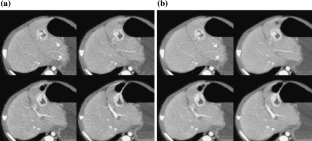

Fig 4.